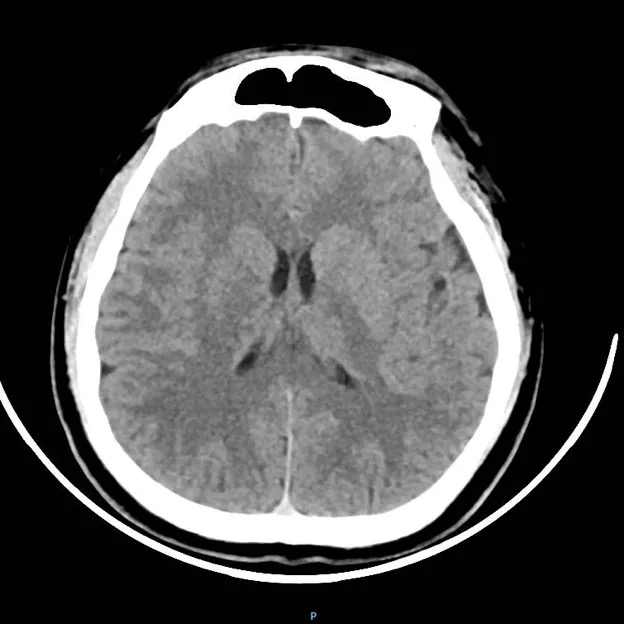

头部CT:

未见明显异常